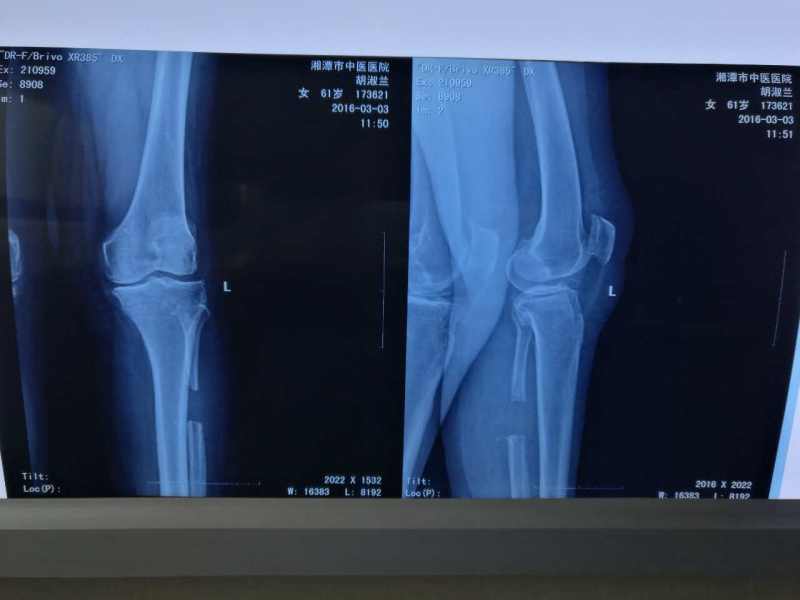

2016年3月1日,我院四病室關(guān)節(jié)與創(chuàng)傷骨科李巍主任、曹謙副主任、陳巍醫(yī)師成功為患者胡淑蘭女士進(jìn)行了左側(cè)腓骨近端截骨術(shù),此例為湘潭市第一例成功采用該類手術(shù)方式治療膝關(guān)節(jié)骨性關(guān)節(jié)炎的病例。此前,胡淑蘭女士雙膝關(guān)節(jié)反復(fù)疼痛有10余年,近一個月疼痛加劇,晚上痛得睡不著覺,甚至痛得半夜起來哭泣,收入院檢查,雙膝關(guān)節(jié)膨大變型,屈伸活動受限,壓痛明顯。